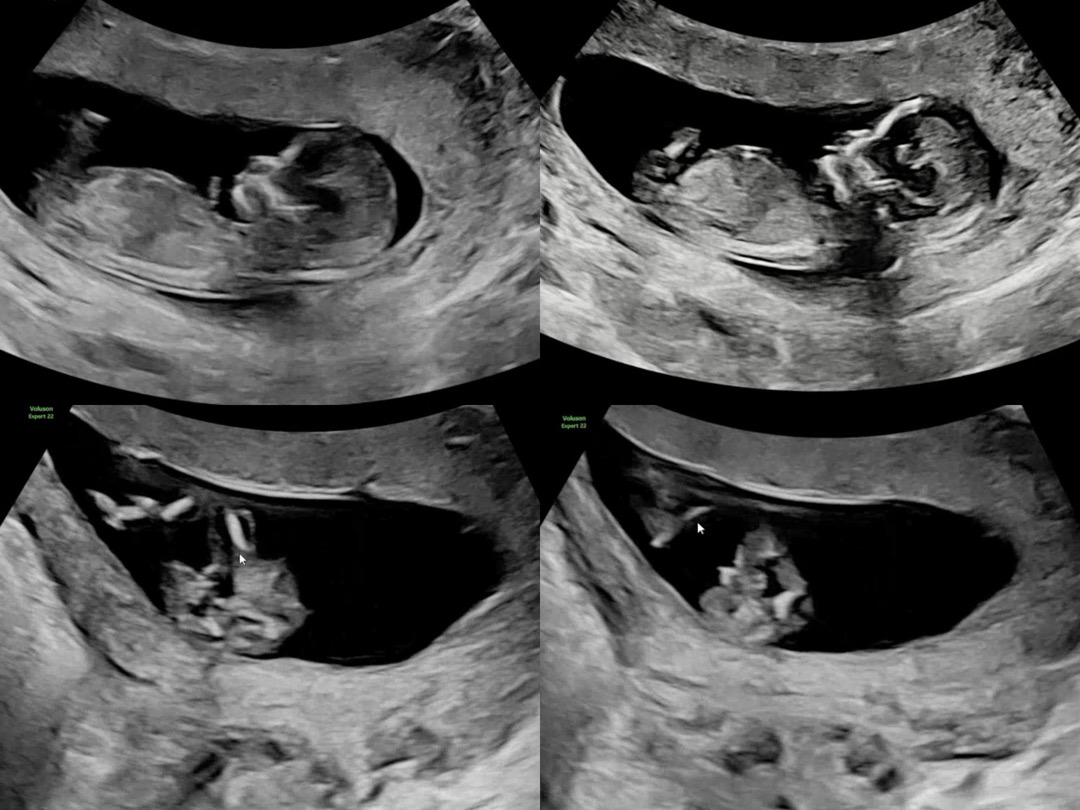

둘째 각도법 봐주실 수 있으실까요😆

첫째는 공주였는데 누나일지 언니일지 사실 지금 병원가면 나오는데 검진일은 멀었고, 조카 옷을 물려받을지 말지 미리 알고싶어서 12주때거 보고 각도법 공부했는데 아무리봐도 헷갈려서 여쭤봐요